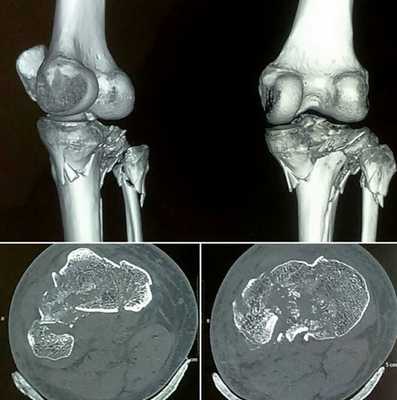

Изменения головки большеберцовой кости на томограмме

Компьютерная томография колена

Остеосаркома бедренной кости на снимке коленного сустава

Для уточнения локализации и размеров патологического очага врач может использовать пространственное изображение области интереса . На основании фотографий, полученных в результате сканирования, реконструируют 3D-модель рассматриваемой зоны. Трехмерная визуализация позволяет оценить характер взаимодействия здоровых и пораженных тканей.